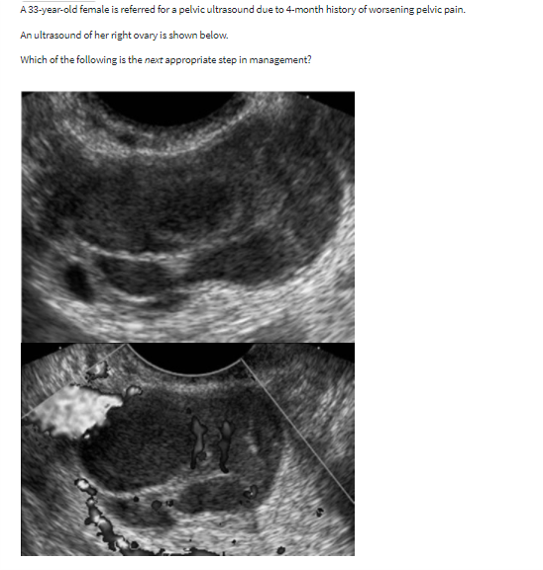

right ovarian mass shown in the image.

Next step?

nothing. this is a simple follicular cyst with a small peripheral follicle (cumulus oophorus)